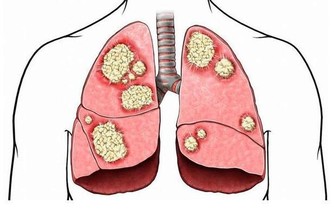

*****三、腳趾增大、增粗*****

正常的人體腳趾在成年後基本上不會發生太大的變化,包括外形、大小等等。但是突然發現多個腳趾有增大、增粗的症狀,腳指甲厚度增加,這就是臨床上所謂的“杵狀指”,杵狀指的出現往往意味著可能患上了肺部慢性疾病。